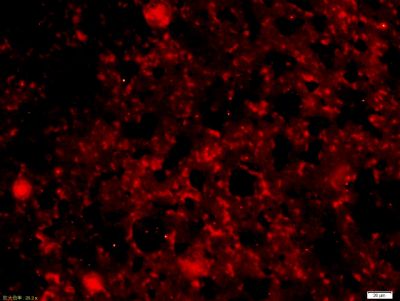

5-羟色胺受体2A免疫组化荧光抗体

产品应用WB=1:500-2000 ELISA=1:500-1000 IHC-P=1:400-800 IHC-F=1:400-800 Flow-Cyt=3ug/Test IF=1:200-800 (石蜡切片需做抗原修复)